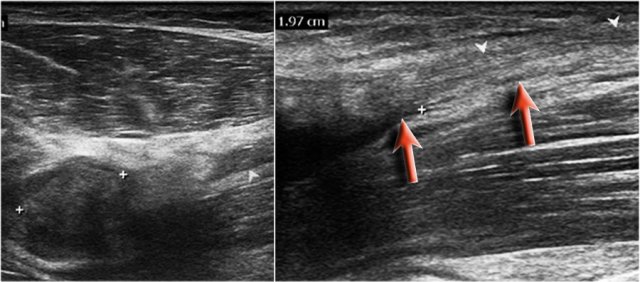

Here are the ultrasound images of a 73 year old male who experienced a sudden pain and a tearing sensation when lifting a box.

There was pain with pronation and supination and tenderness anteriorly proximal to the elbow joint.

No ecchymosis or palpable mass.

On the sagittal image the tendon is thickened, but distally the tendon is lost.

MRI examination was performed.

Now look at the MR-images and try to figure out if the tendon is retracted and whether there is a partial or complete tear...

Well on the sagittal image it looks as if the tendon is completely thorn, but continue with the next images.

Tear of distal biceps tendon

There is a complete tear, because if we follow the tendon all the way to the radial tuberosity, we can see that the tendon does not attach there (green arrow).

There is only fluid.

The reason why the tendon is not retracted is because the broad bicipital aponeurosis - also known as lacertus fibrosus - is still intact (red arrow).

The distal biceps tendon not only inserts to the radial tuberosity, but also via the lacertus fibrosus into the fascia of the flexor pronator mass on the medial side of the forearm.

The distal tendon of the biceps is encircled on the upper left image.

When the aponeurosis is also thorn, then the tendon retracts and you get an obvious swelling in the arm caused by the contracted biceps muscle.